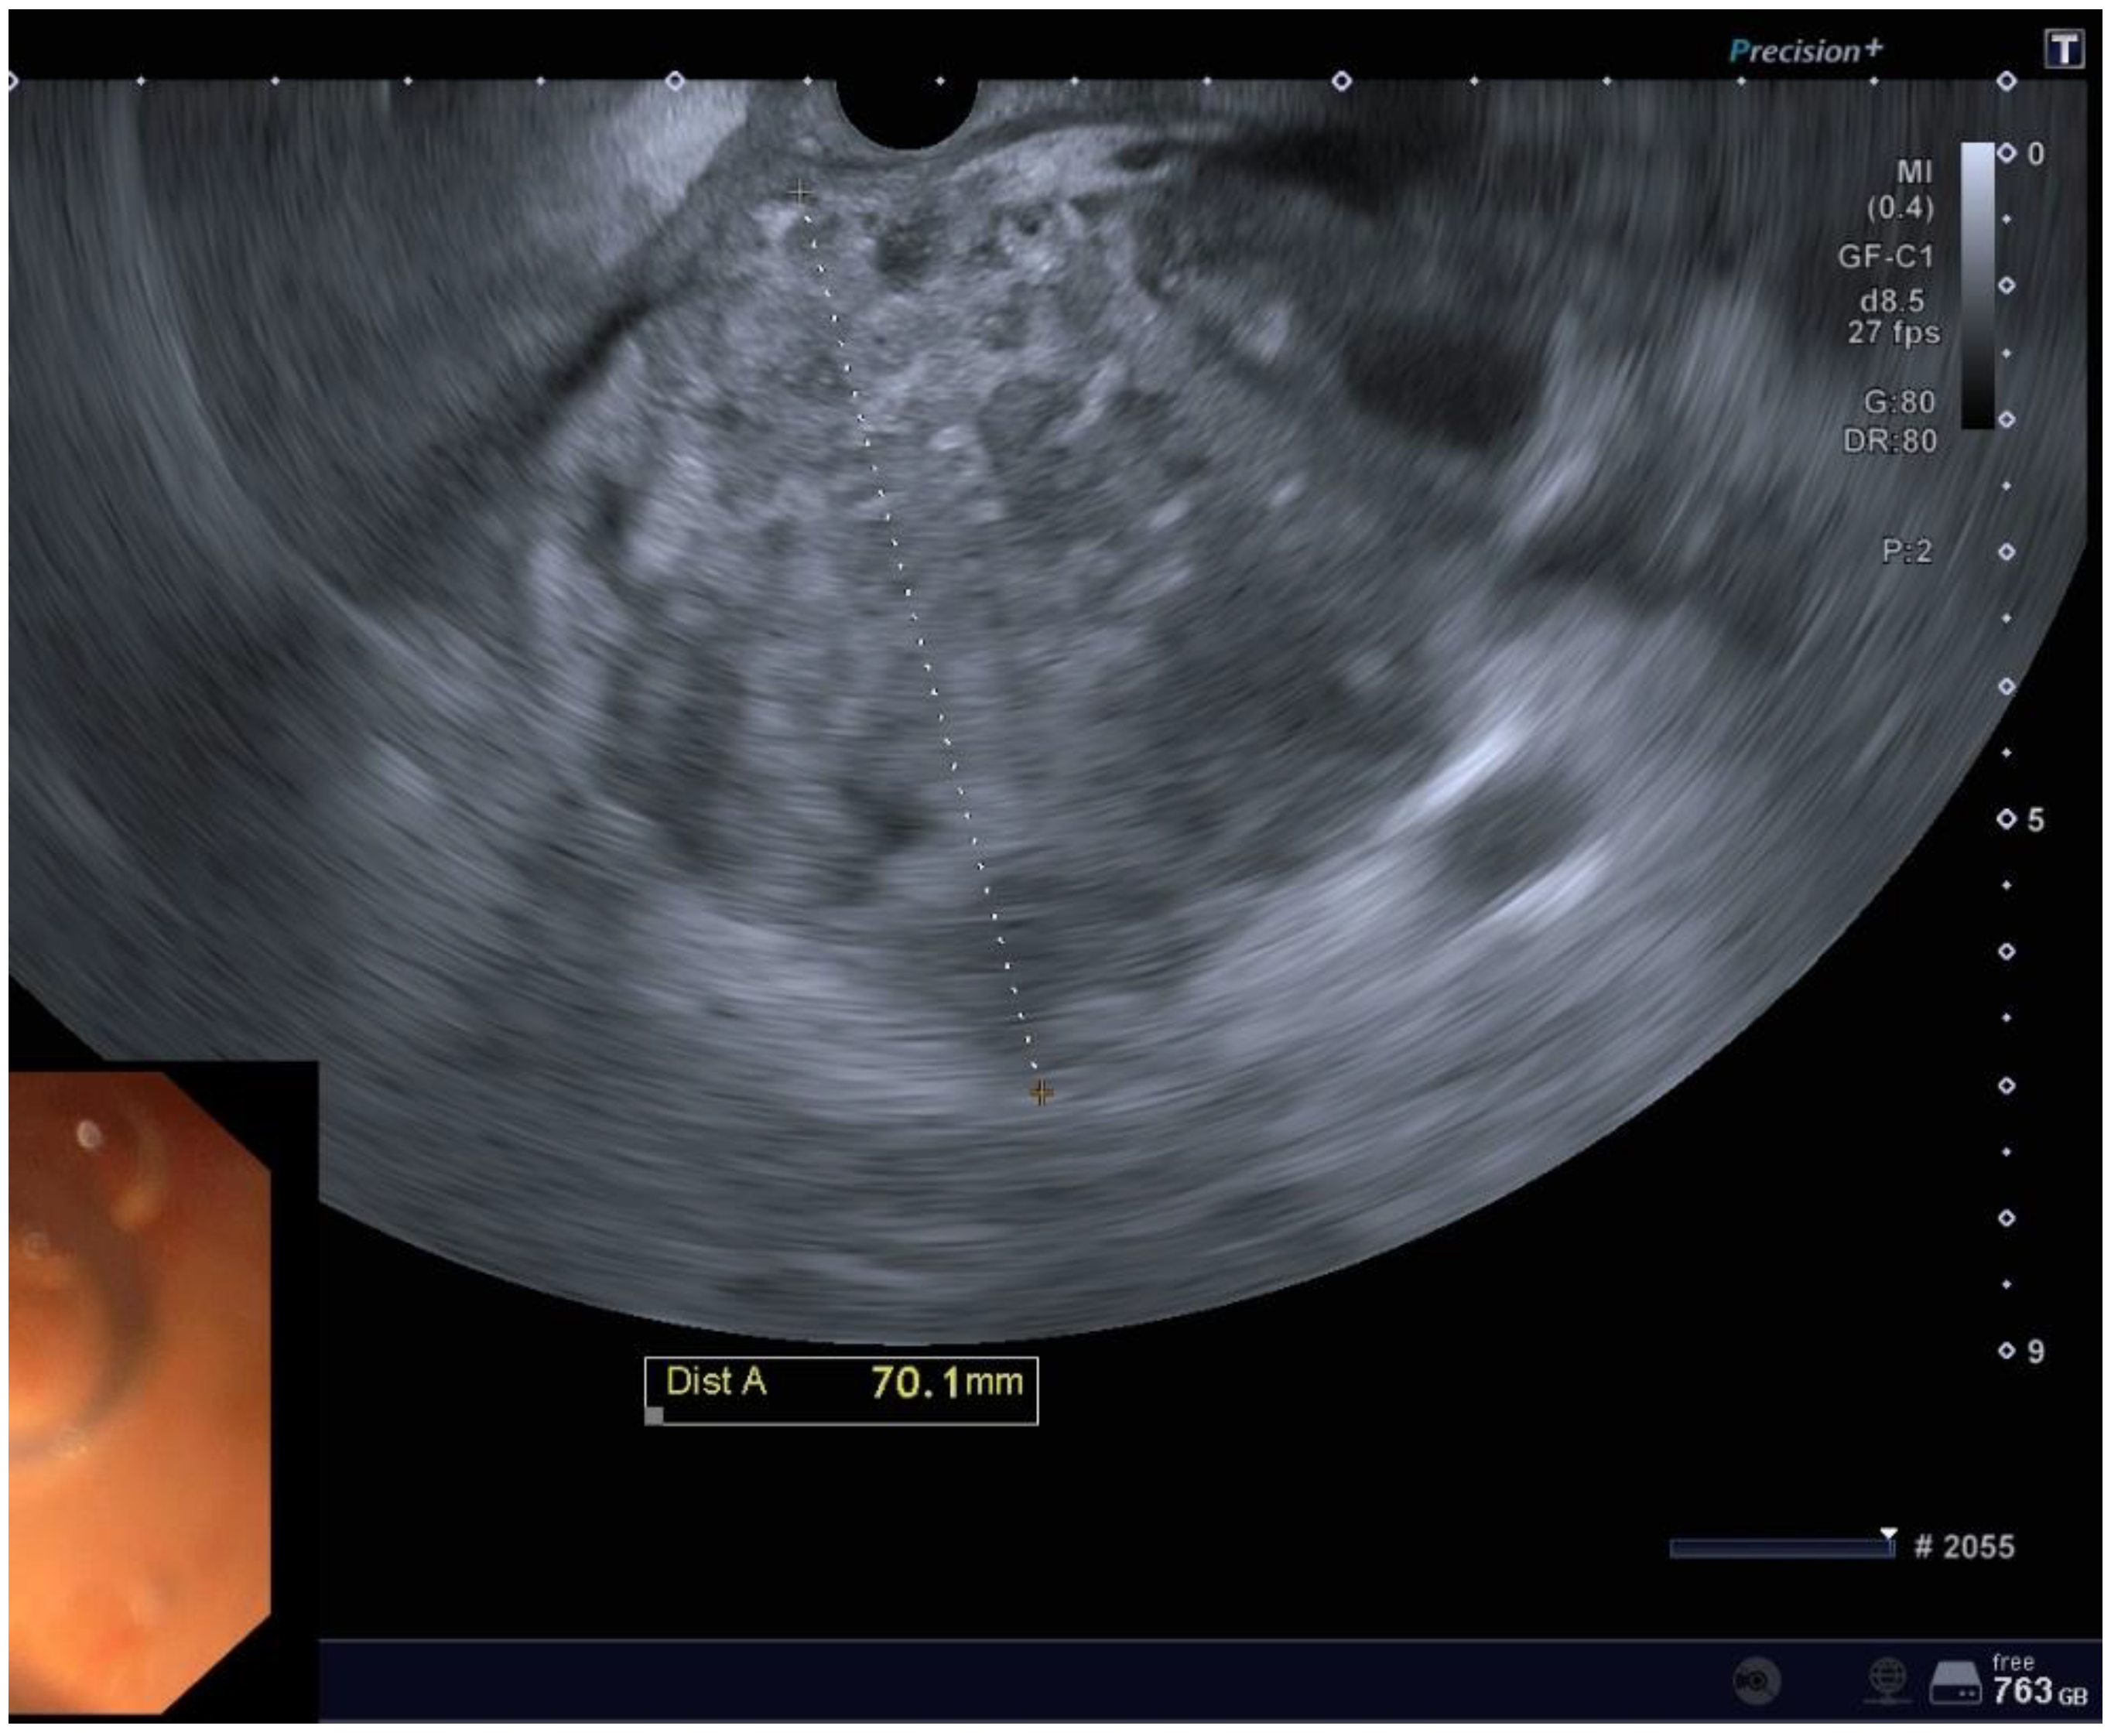

Figure 1. EUS imaging of a POFC.

Preprints 154291 g001

The mean size of the POFCs on EUS evaluation was 88.8 mm in width (SD 61.8) and 77.2mm in length (SD 45.7).